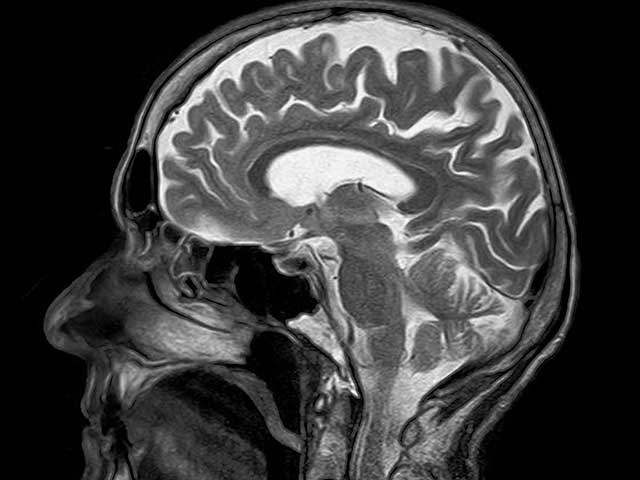

How Do You Prove a TBI?

How do you prove you have a TBI? If you have suffered a traumatic brain injury (TBI), it is probable that you are not acting like you once did. You may be struggling with memory loss, confusion, and sometimes impulsivity. You might also be experiencing frequent headaches, sleep problems, and dizziness. So, how do you prove a trau[...]